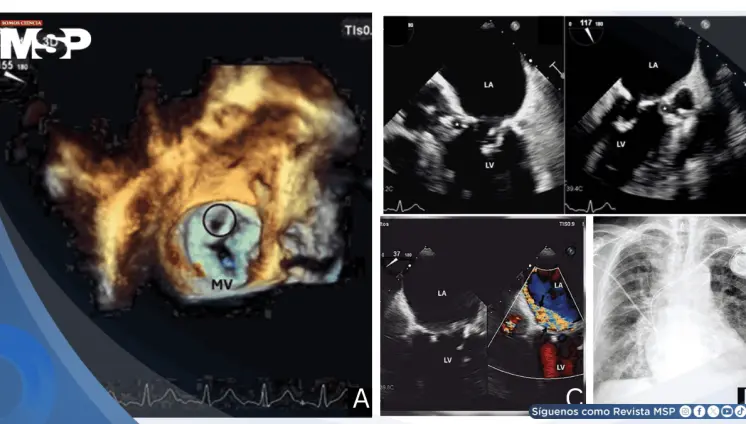

Endocarditis de Staphylococcus epidermidis tras implante de marcapasos causa pseudoaneurisma mitroaórtico